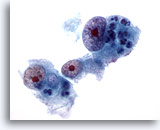

画像 5

肝FNA – 良性胆管細胞

良性胆管細胞の集塊。蜂巣状に配列し、均一な小型の核がみられます。

20倍

画像 5

肝FNA – 良性胆管細胞

良性胆管細胞の集塊。蜂巣状に配列し、均一な小型の核がみられます。

20倍